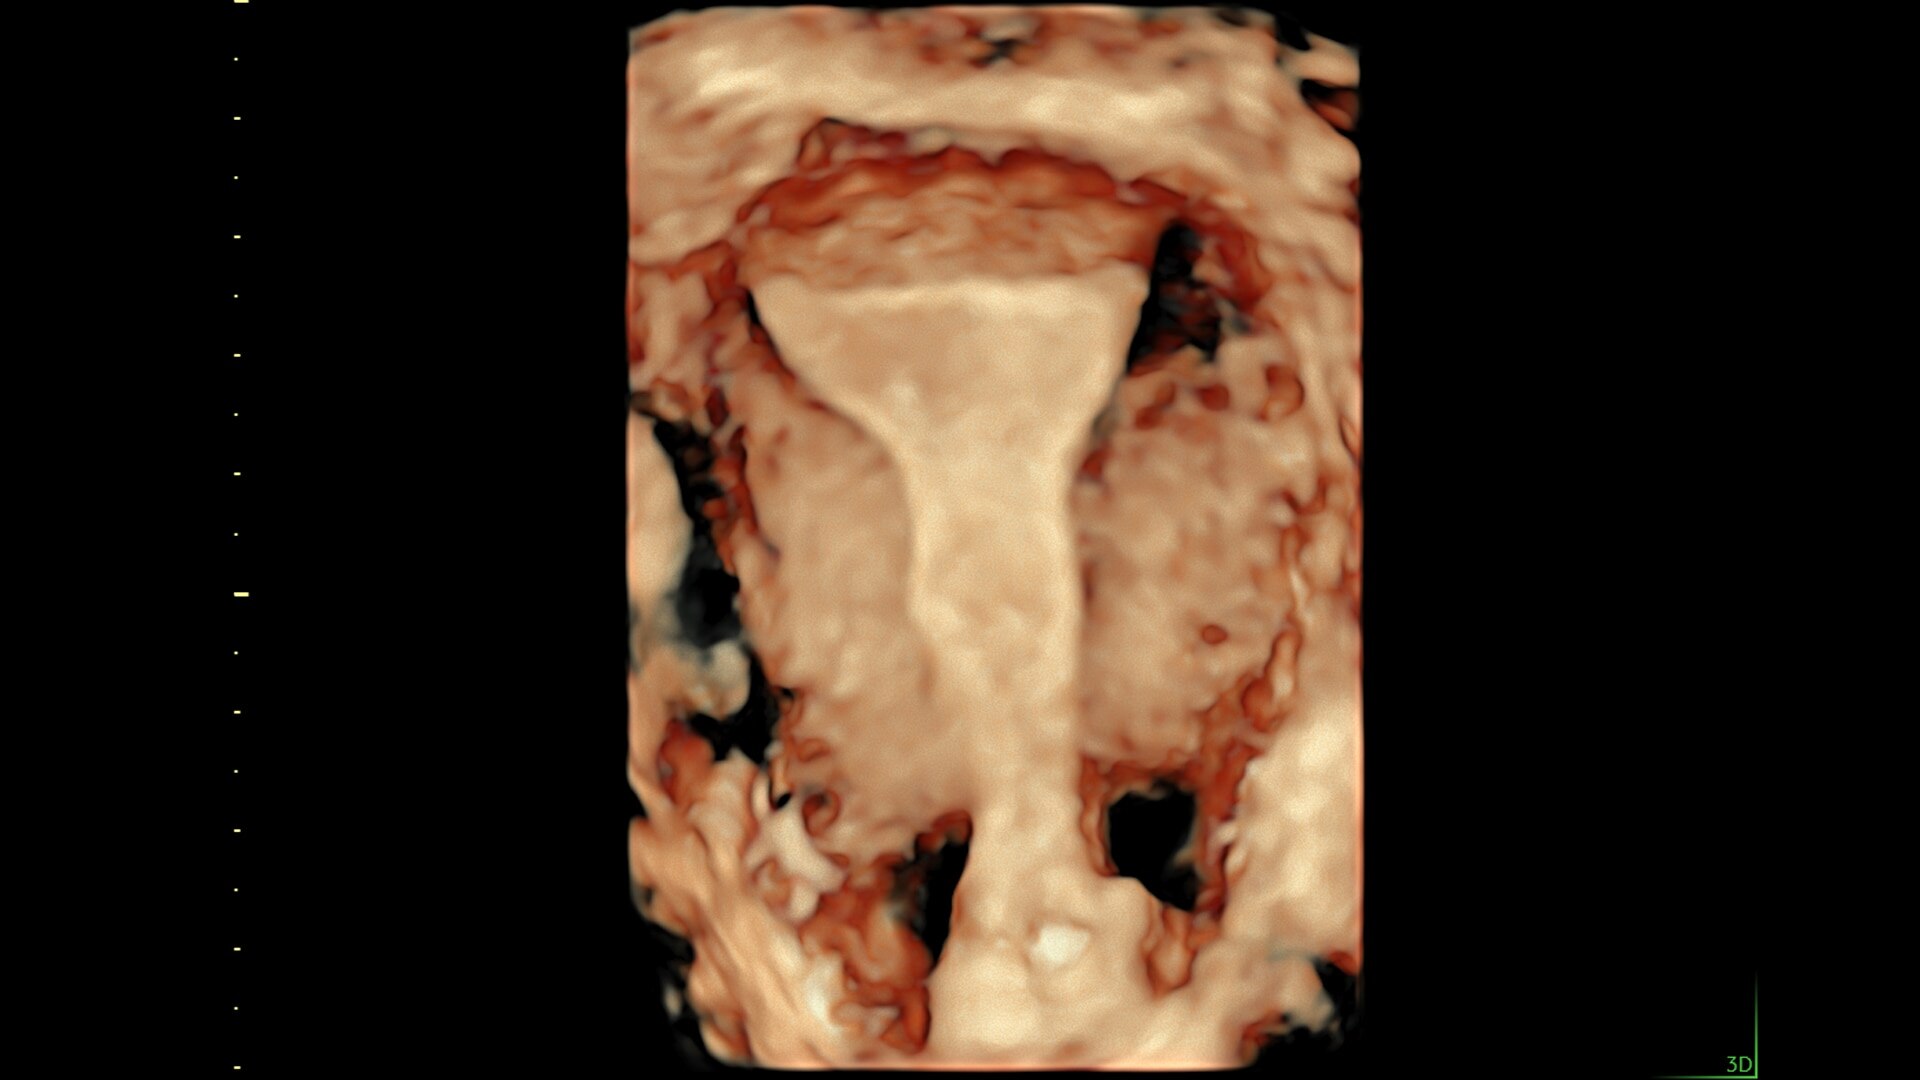

83%

Reduce keystrokes by 83% with 3D Spine Trace